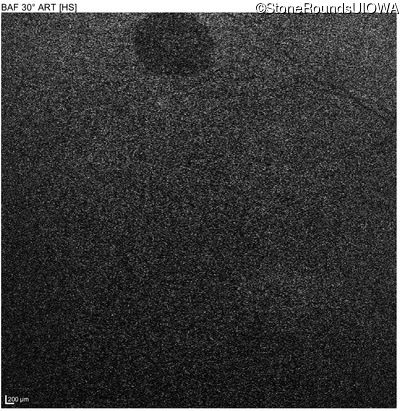

Blue Autofluorescence - Right - 10/300 sc

Exemplar